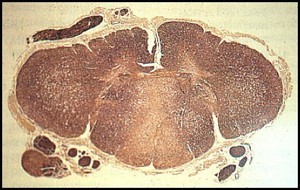

A 75 year old man begins to develop tremors and his wife notices that he seems to walk slower around the house. On neurological exam her demonstrates slower movements and writes in smaller handwriting than normal. Based on the gross speciment below, what would his diagnosis be?

Parkinson’s disease:

Pathology:

Loss of pigmented dopaminergic cell in the substantia nigra pars compacta and the formation of Lewy bodies in the brainstem.